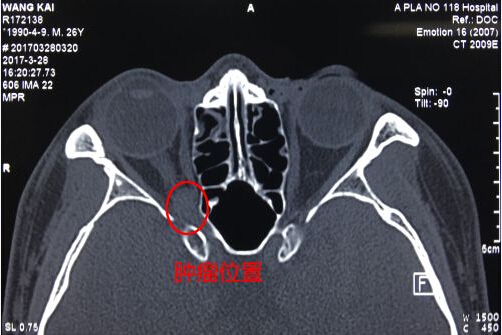

温都讯 宁波26岁青年小王右眼视

力越来越模糊,看不清,经眼眶

CT与核磁共振检查发现原来是眼

眶眶尖深部视神经入眶口处长了

一个黄豆大小的肿瘤,其视力被

肿瘤慢慢地“蚕食”了。曾先后至

3月10日,他找到吴文灿教授。经

过仔细检查,吴文灿认为小王右

眼视力下降的原因是他右侧眼眶

眶尖深部视神经入眶口处长了一

个小肿瘤,是该肿瘤压迫了视神

经造成视神经功能下降。要想保